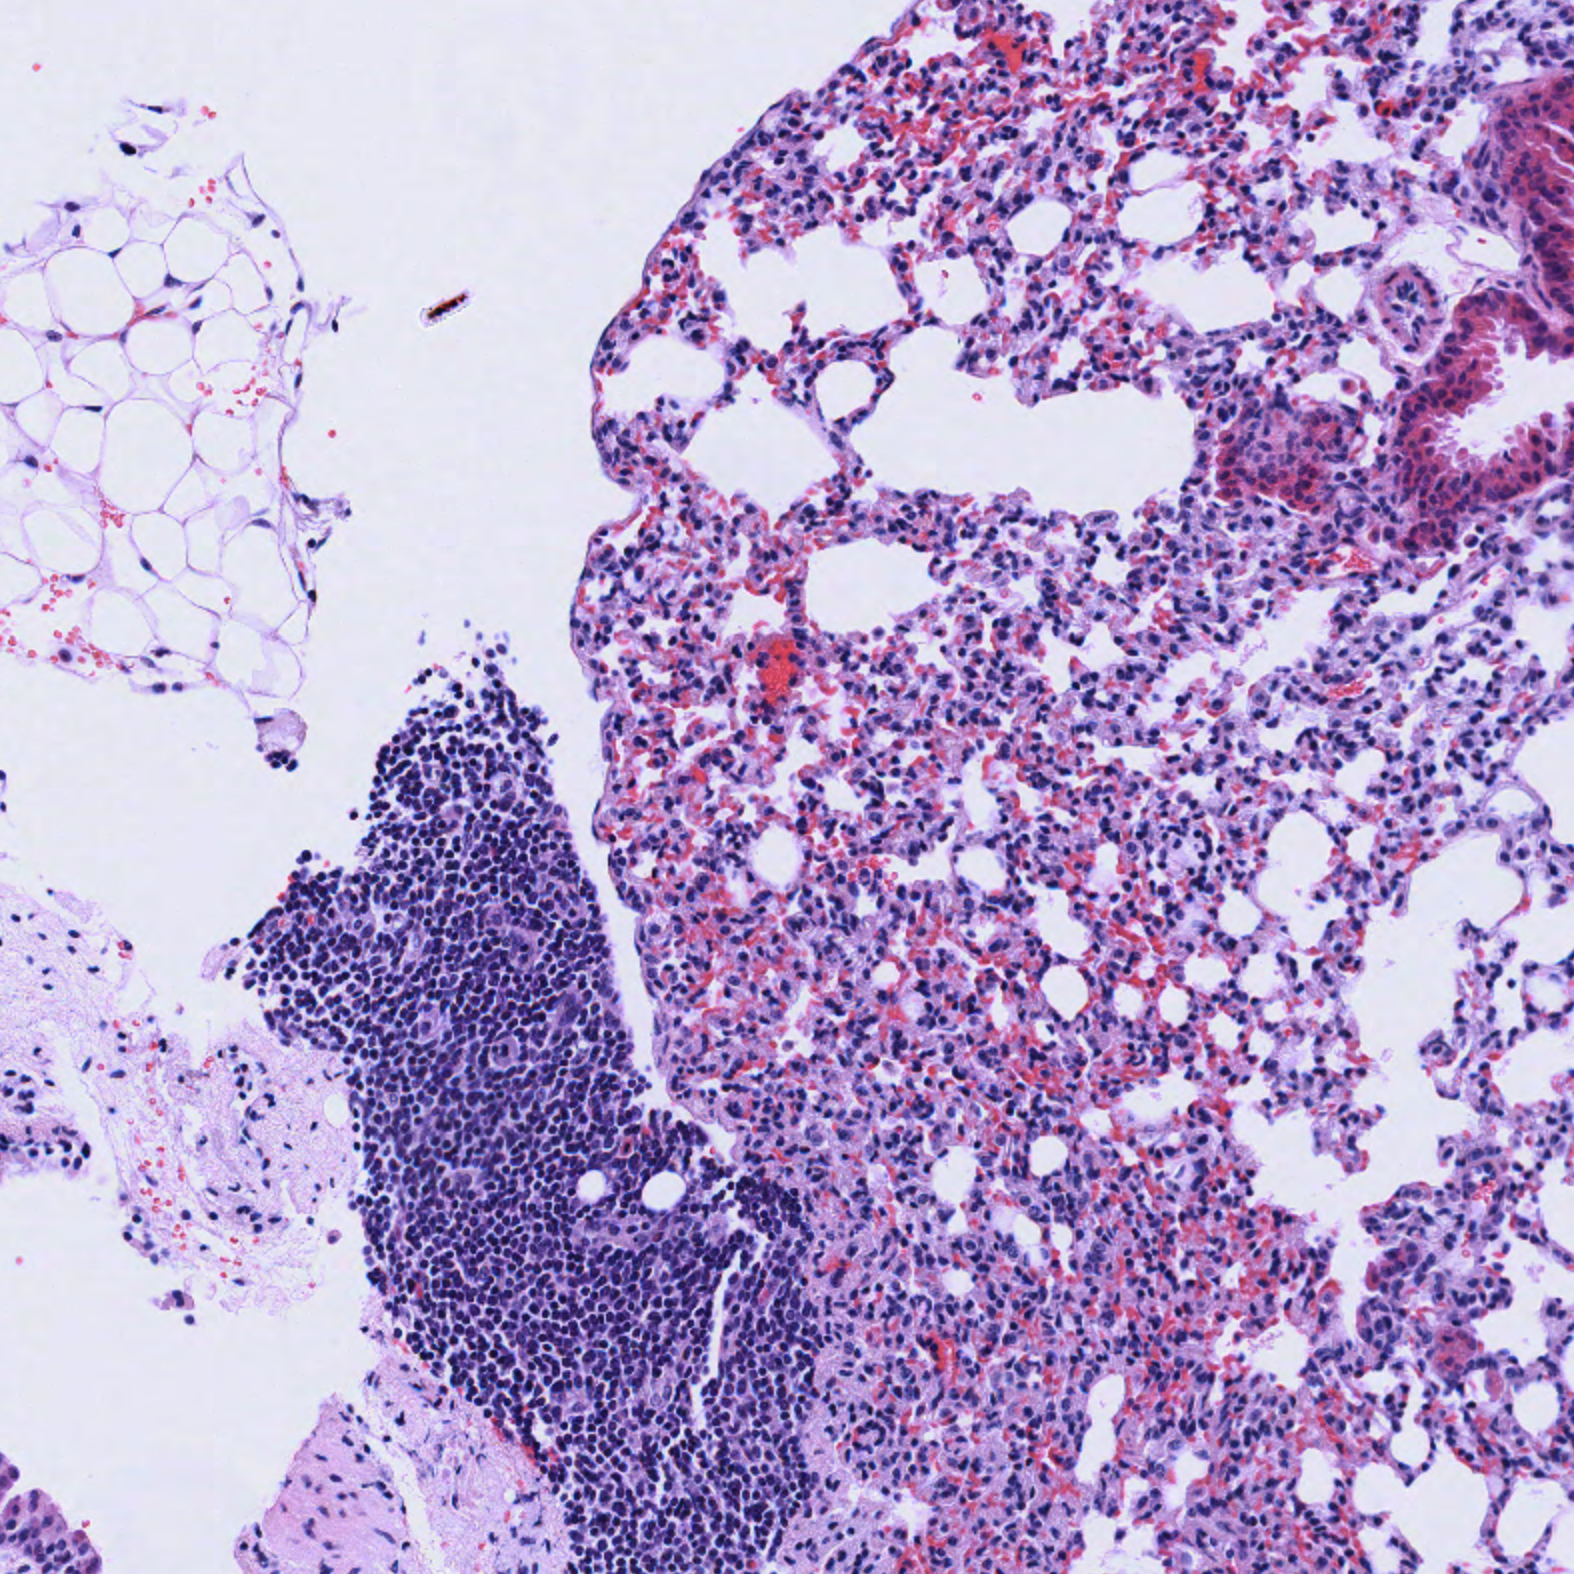

Lung

| Lung_H&E_02.svs Lung_H&E_02.png |

The stroma surrounding the bronchioles in blue/green shown in the pentachrome-stained slide is clearly visualized. In cases of chronic bronchitis, the use of the pentachrome stain kit might allow for better visualization of fibrosis and collagen.

Please note: mouse tissue does not have cartilaginous rings in the lungs and do not have bronchi.